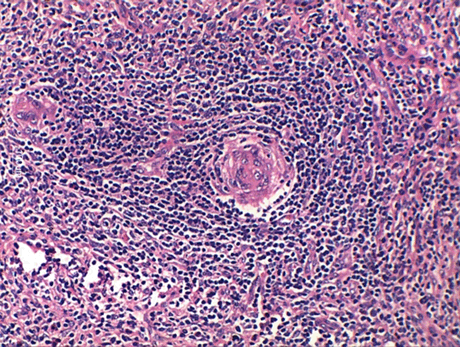

The patient was planned for surgery and underwent left thoracotomy with excision of mass. Peroperatively, there was a 15x10x8 cm soft fleshy tumor with areas of calcification with extensive feeding vessels from parietal pleura and posterior chest wall. The tumor was abutting on left subclavian artery and partially adherent to it; and could not be resected in toto. The gross examination of the operative specimen revealed a 10.5x6.5x4.5 cm mass; the cut surface of which was soft and variegated with areas of calcification. Microscopically, (Figure 3) dense population of mature lymphocytes was noted with inconspicuous epithelial component, well-developed Hassall's corpuscles, perivascular spaces, fibrous septae and foci of medullary differentiation. There was no necrosis and no invasion. Based on these findings, a histological diagnosis of thymoma, WHO Type B, predominantly cortical type was made. In view of incomplete resection, the case was discussed jointly in a tumor board and the consensus was to treat the patient with postoperative radiotherapy (RT). The patient received adjuvant RT to mediastinum by three-dimensional conformal RT technique on a linear accelerator to a dose of 5400 cGy in 27 fractions. He tolerated RT well without any significant toxicity and break in treatment. The patient is disease-free clinically and radiologically at two years of regular follow-up.

Figure 3: Thymoma WHO Type B. Dense population of mature lymphocytes with inconspicuous epithelial component (medullary differentiation), well developed Hassall's corpuscles and perivascular spaces (H&E stain, x400).